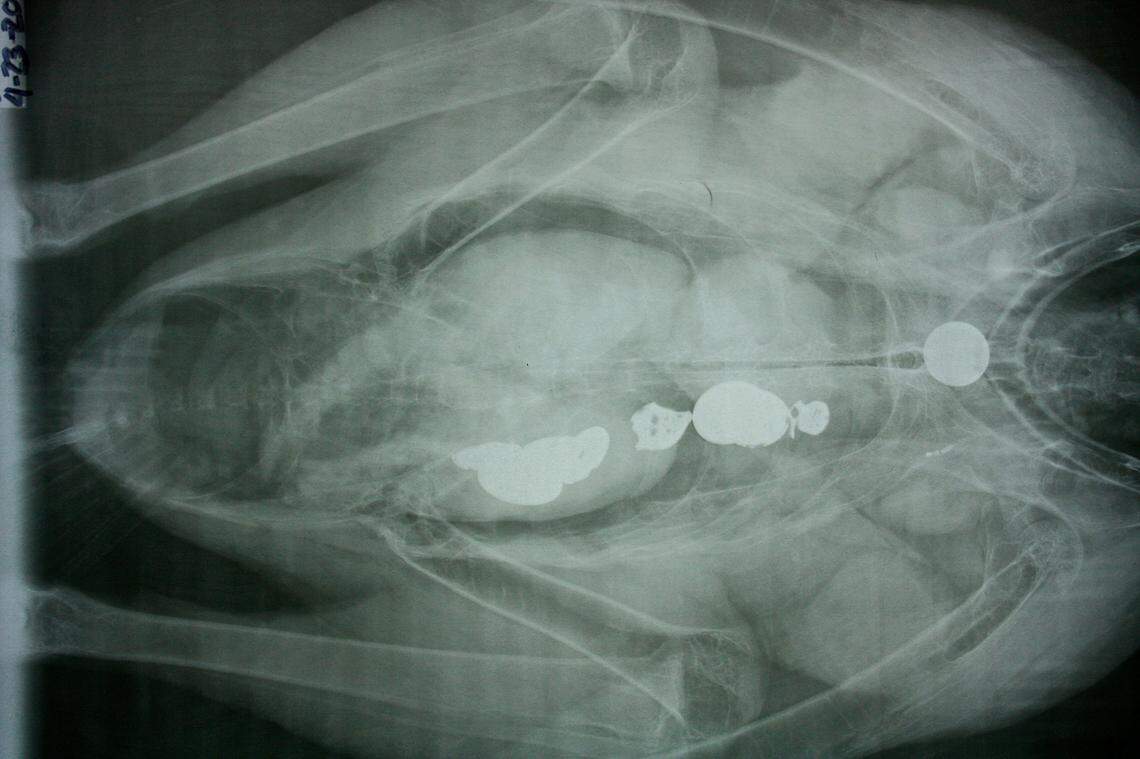

Coins are shown in a California condor’s digestive tract. The birds can die if they eat metal objects, park officials said.

Park officials shared a photo of a condor’s digestive tract filled with coins and said it underwent an operation to have them removed.